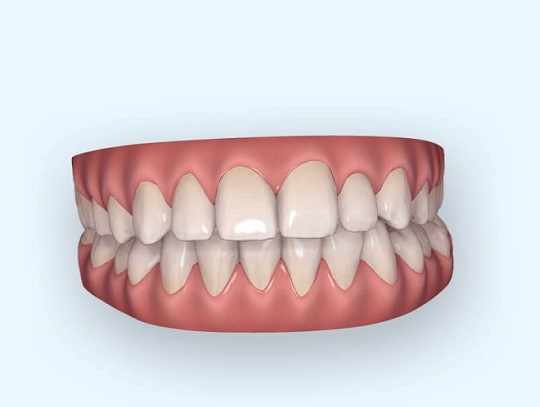

Do niedawna modele uzyskiwano po odlaniu z gipsu, pobranego w ustach na łyżce wyciskowej specjalną masą wycisku. Obecnie korzystamy ze znacznie przyjaźniejszego dla pacjenta urządzenia – skanera 3D. Uzyskujemy w ten sposób przestrzenny model uzębienia pacjenta z zarejestrowanym ich wzajemnym ułożeniem do siebie. Dzięki temu możemy wstępnie zasymulować jak będzie pacjent wyglądał po leczeniu ortodontycznym.